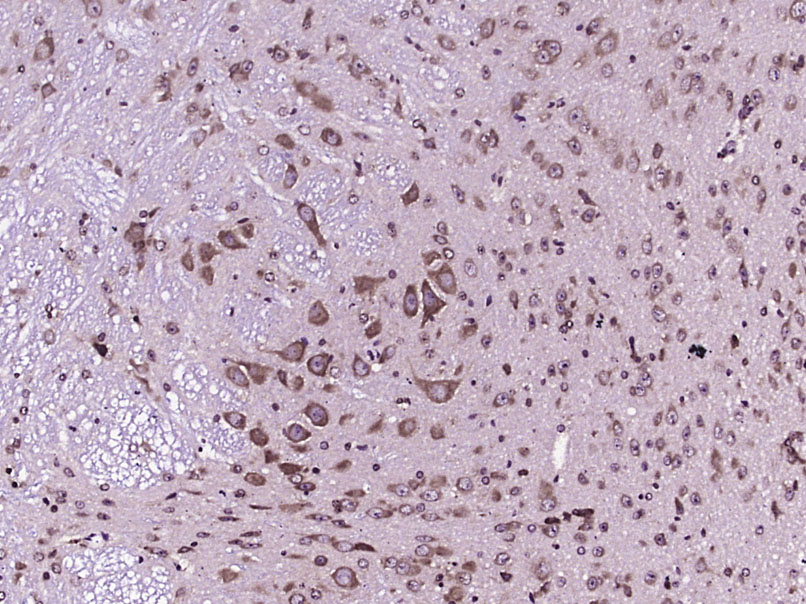

Paraformaldehyde-fixed, paraffin embedded (Mouse brain); Antigen retrieval by boiling in sodium citrate buffer (pH6.0) for 15min; Block endogenous peroxidase by 3% hydrogen peroxide for 20 minutes; Blocking buffer (normal goat serum) at 37°C for 30min; Antibody incubation with (CNR2) Polyclonal Antibody, Unconjugated (bs-2377R) at 1:400 overnight at 4°C, followed by operating according to SP Kit(Rabbit) (sp-0023) instructionsand DAB staining.